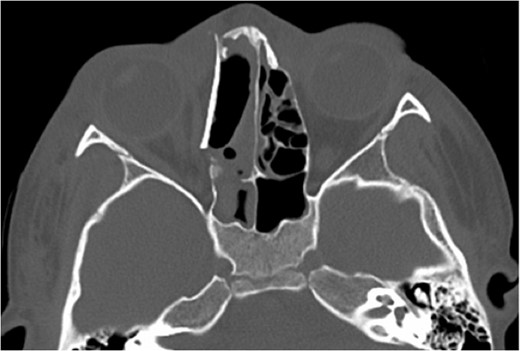

A 6-year-old boy with a background of asthma presented to a tertiary paediatric unit in May 2016 with a 3-day history of right eye pain, proptosis and erythema under the care of the ENT team. A provisional diagnosis of a periorbital cellulitis was made secondary to ethmoid sinusitis and management with intravenous antibiotics (ceftriaxone), intranasal steroids, saline douches and topical oxyxlometazoline was initiated. Ophthalmological assessment demonstrated normal colour vision, acuity and light reflexes bilaterally but also proptosis-related ophthalmoplegia. Computed tomography (CT) imaging of the orbits and paranasal sinuses demonstrated complete opacification of the right-sided paranasal sinuses and compromise of the right frontal and ostiomeatal unit. In addition there was an expansile abnormality centred on the ethmoidal labyrinth with bony remodelling of the lamina papyracea and a subperiosteal collection adjacent to the medial orbital wall (Figs 1 and 2). The most likely diagnosis was felt to be an infective process with mucopyocele formation complicated by a subperisoteal post-septal collection. An MRI scan with gadolinium of the orbits and sinuses confirmed the unilateral pattern of sinus opacification within the right frontal, ethmoids and maxillary sinus. The lesion demonstrated multiple fluid–fluid levels and peripheral enhancement (Figs 3 and 4). The patient was treated by endoscopic drainage of the lesion, which revealed only blood. He initially had some improvement of his proptosis but recurred within a few days and so further, more extensive endoscopic debridement was performed.

Axial non-contrast CT demonstrating an expansile lesion centred on the right-sided ethmoidal labyrinth (long white arrow) with remodelling of the lamina papyracea (short white arrows).